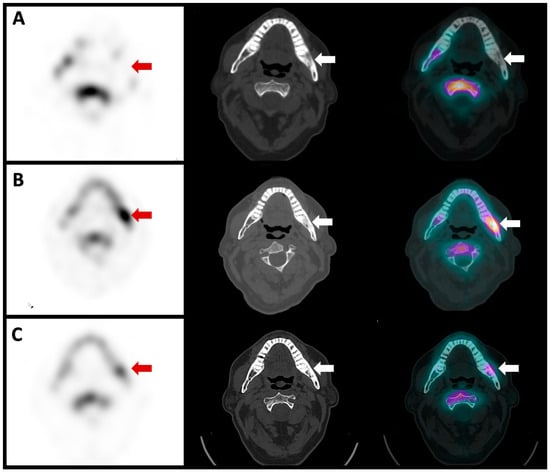

Figure 4. Planar scintigraphy imaging of a 67-year-old patient who had the extraction of tooth 38 with transient improvement. A few months later, the same pain recurred and was difficult to control with multiple analgesic attempts. Biological results showed no infectious signs. The anterior planar image acquired 6 h after the intravenous injection of anti-granulocyte antibodies showed no radiotracer uptake in the left mandibula ((A), red arrow). Likewise, no radiotracer uptake was seen in the left mandibula on the anterior left profile image acquired 24 h after the radiopharmaceutical injection ((B), red arrow). The blood pool phase (anterior view) of the bone scan showed no left mandibular hyperemia ((C), red arrow). On the other hand, the delayed image of the bone scan (anterior view) showed marked radiotracer uptake ((D), red arrow).

Figure 5. Single-photon emission computed tomography (SPECT), computed tomography (CT) and fusion images of the same patient showed no anti-granulocyte antibody uptake in the left mandibula ((A), red and white arrows). The images of the CT scan showed reactive osteosclerosis with no lytic or soft tissue collection suspicious of active infection (middle image, red and white arrow). The bone scan SPECT/CT showed intense radiotracer uptake in the left mandibula ((B), red and white arrows), indicating active osteoblastic activity. The patient was treated us biphosphonates and a follow-up bone scan SPECT/CT was repeated two years later, which showed a marked decrease in left mandibular radiotracer uptake ((C), red and white arrows).